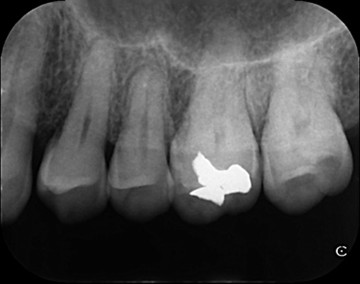

初診時歯周ポケット6mm、左上4番に骨吸収を認める

歯周病の好発部位である上顎第一小臼歯近心面における骨吸収に対して再生療法を行ったケース。一般的に根面溝という溝があり歯石の沈着が生じやすい。また溝の存在により術後に歯肉と歯根の付着が生じにくいため、今回はEr:YAGレーザーにて血餅形成を行い組織の安定化を図った。